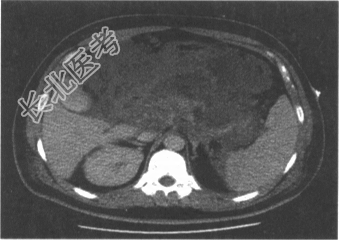

- 多项选择题4.患者入院1周后,生命体征趋于稳定, 临床症状缓解,无发热, 复查CT见下图。考虑患者目前出现的并发症是

A、急性胰周液体积聚

B、急性胰周液体积聚伴感染

C、急性坏死后液体积聚

D、包裹性胰腺坏死

E、胰腺假性囊肿

F、胰腺假性囊肿伴感染

关注下方微信公众号,搜题查看答案